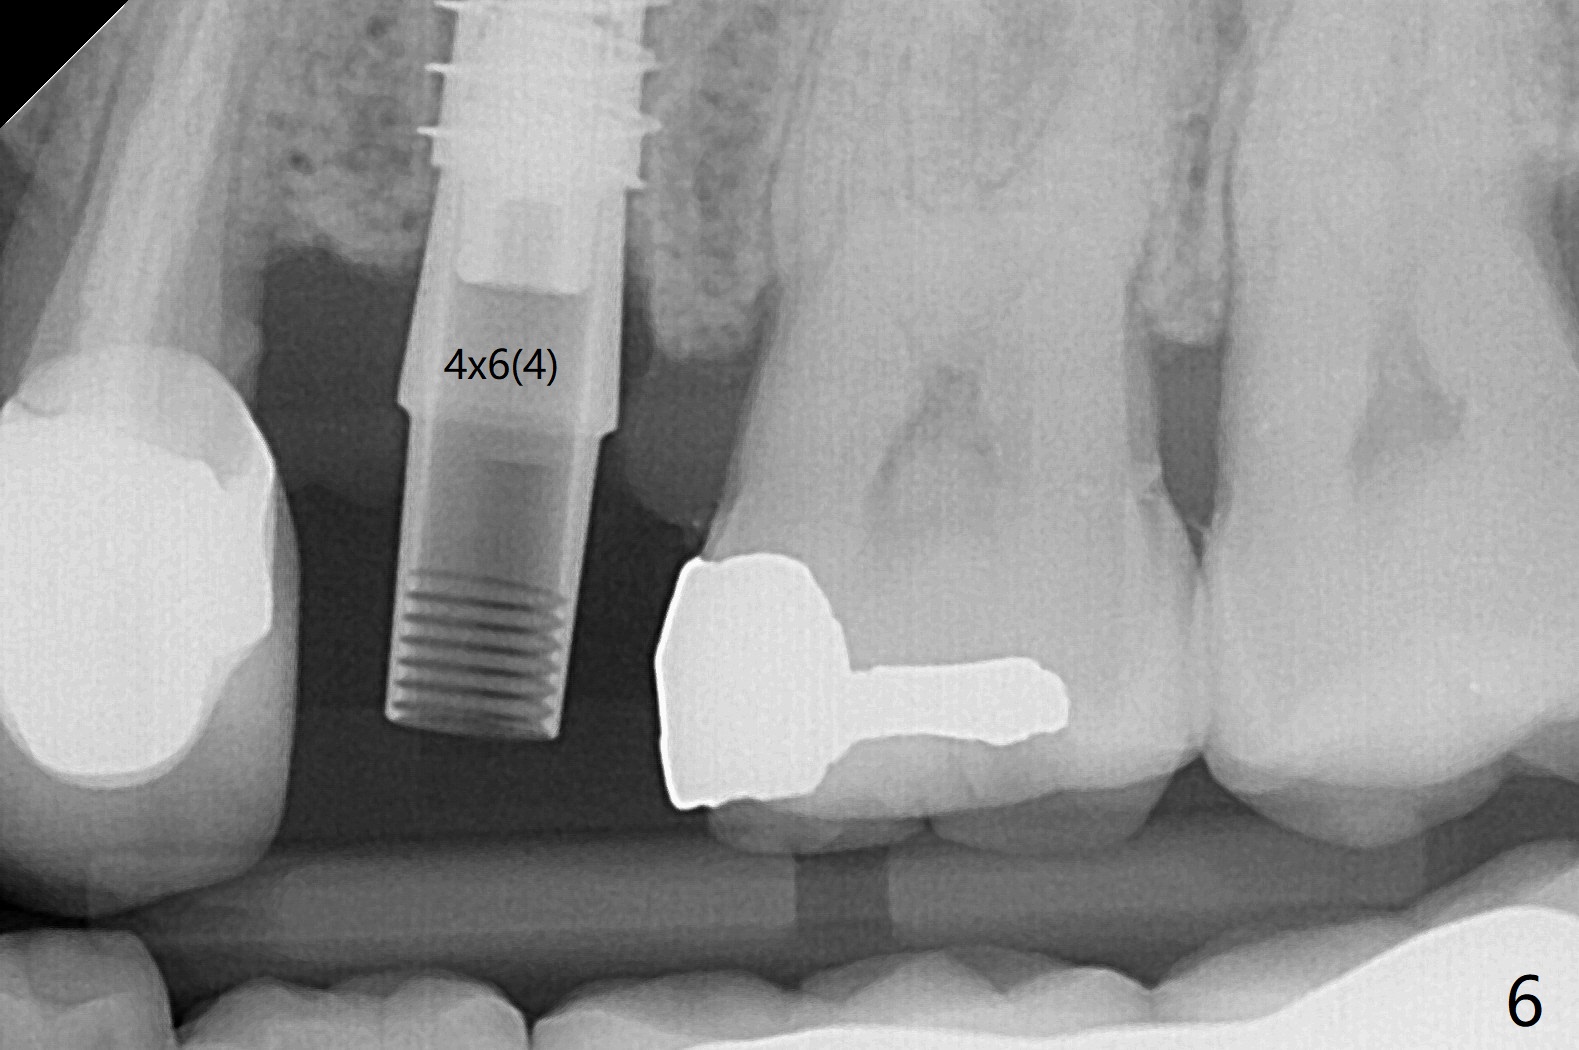

害怕病人局麻药很慢起效,术中身体会动,术中决定减小右下6,7植体直径0.5毫米(与导板设计相比),一旦植体越过牙槽嵴顶骨皮质,稳定性突然减低(图一)。尽管扭力10-15Ncm,为了避免二期手术,放置愈合基台(图二),6基台没有就位(箭头),因为植体种太深了,牙槽骨阻挡(*)基台就位。当取出6基台时,植体一起旋出,重新植入时,就没有种那么深(图三:箭头,与图一,二对比)。由于扭力低,只好放置愈合帽,骨粉(*),GEM Cap(6-9月胶原膜)和牙周胶水。由于导板设计缘故,左上5拔除,种植后,才开始左上3一段式植体植入(图四),5也植入太深(图五),必须放置最小直径最长袖(cuff)的基台(图六),今后导板即刻植牙先不要到达设计深度。术后一周CT显示尖牙植体位于牙槽骨内(图七 (>:腭侧牙槽嵴))。Bone graft fills in the buccal apical defect at #13 one week postop (Fig.8 <). 术后两个月左上3临时牙冠折裂,5松动(图九,十),后者取出衬里,软组织愈合。术后8个月左上3,5取模,右下6 uncover,愈合帽表面覆盖骨质,把7号牙愈合基台放到6号牙上,而7号牙放置4.5x4(4)毫米修复基台,固定牙周敷料,这样6号牙伤口不必缝合。术后8.5个月右下6放置4.5x7.5(4)毫米基台,发现7基台没有就位(图十一:箭头),通过旋转7 基台,终于就位(图十二),螺丝往下移位(与图十一:横线对比),但是基台边缘太低,不利于取模。改用5.5x4(5)毫米UF基台,临床上不能就位,局麻使用5.5毫米Profile Drill后,才能就位(图十三),螺丝下端超越最低螺沟(横线)。